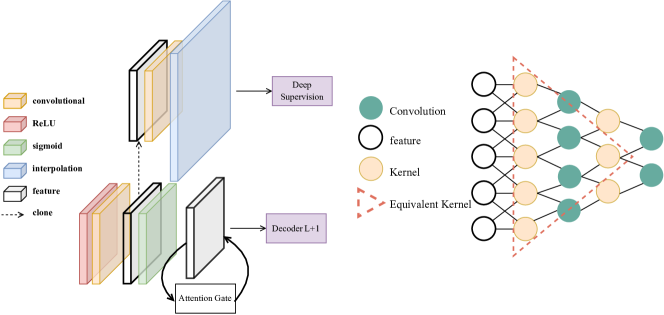

The original MHEX framework [13] employs deep supervision [23, 24] and attention gating mechanisms [25] to enhance performance. During the explanation phase, an equivalent transformation matrix is constructed.

where is a convolution followed by ReLU activation, and denotes the sigmoid function applied in the attention gate. The final deep prediction is computed via . For simplicity, biases are omitted in our implementation.

The MHEX+ module in EU-Nets is depicted on the left side of Figure 1.

3.3 Equivalent Convolutional Kernel & Salience Map

We extend the principle to convolutions. Given two consecutive layers and , their equivalent kernel is computed as:

where represents the output channel corresponding to a specific class. is part of the Attention Gate, while is responsible for deep prediction.

In this way, multiple convolutional operations are consolidated into a single equivalent transformation. The Equivalent Convolutional Kernel enables efficient Class Activation Map (CAM) generation:

where represents the activation map of the -th channel.

It is important to note that the time complexity of Grad-CAM is , whereas MHEX+CAM has a time complexity of , where denotes the , which is a constant usually.

The right side of Figure 1 illustrates the Equivalent Convolutional Kernel.